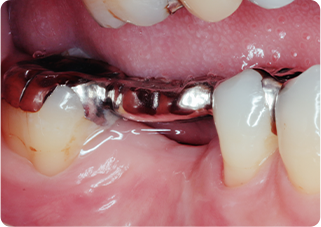

矯正的挺出・歯冠長延長術・セラミッククラウン症例①

術前

MTM、歯冠長延長後

術後

| 主訴 | むし歯の歯を抜きたくない |

|---|---|

| 治療期間/回数 | 5ヵ月、10回 |

| 価格(税込) | 154,000円(税込) |

| リスク・副作用 | セラミックの破損・脱離が生じる場合がある |

| ポイント | 通常だと抜歯と診断されるが、局所矯正と外科処置を行い、歯根を持ち上げることで、被せ物が可能になった。歯根を持ち上げたことにより長期的に安定した被せ物が可能になる。 |